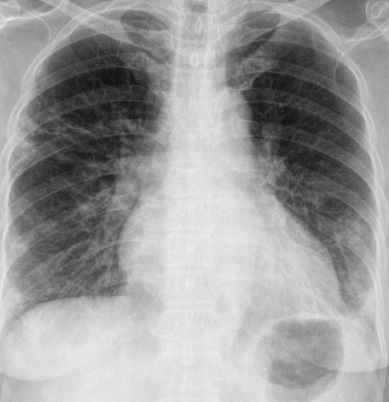

Figure 6 presents image examples for each class retrieved from the RYDLS-20 database. It is worth to mentioning that we have no further information concerning the CXR images with regarding the CXR machine used to take the image, as well as the origin, age and ethnicity of the people whose these images belong to.

Refer to caption

(a) Normal.

(b) COVID-19.

(c) SARS.

(d) MERS.

(e) Pneumocystis.

(f) Streptococcus.

(g) Varicella.

Figure 6: RYDLS-20 image samples.